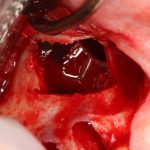

Кстати, обрати внимание на ширину альвеолярного гребня (левая картинка). Она чуть меньше 3 мм. Это объясняет, почему я засомневался в возможности установки имплантатов одновременно с остеопластикой. Понятно и без КЛКТ.

Наперво, мне нужно удалить разрушенный зуб и получить костный аутотрансплантат.

Возвращаемся к основной операционной области. Еще раз посмотрим на альвеолярный гребень, поофигеваем от его ширины и моих грандиозных планов: